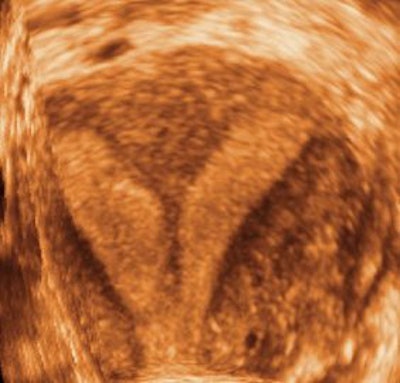

| Three-dimensional ultrasound images showing submucosal fibroids. Images courtesy of Dr. Beryl Benacerraf. |

Other instances in which 3D is helpful include identifying the presence and nature of submucosal fibroids, effectively performing a "virtual hysteroscopy."

In one study of 43 patients with abnormal uterine bleeding, Benacerraf and colleagues found that a 3D coronal view of the uterus was helpful in detecting polyps or fibroids in 35% of cases. The polyps were suggested but ill-defined on 2D ultrasound, she said, and 3D clarified the findings.

The same study also found that turning on the 3D capability wasn't necessary or worthwhile if the 2D scan appeared normal or showed a well-defined finding.